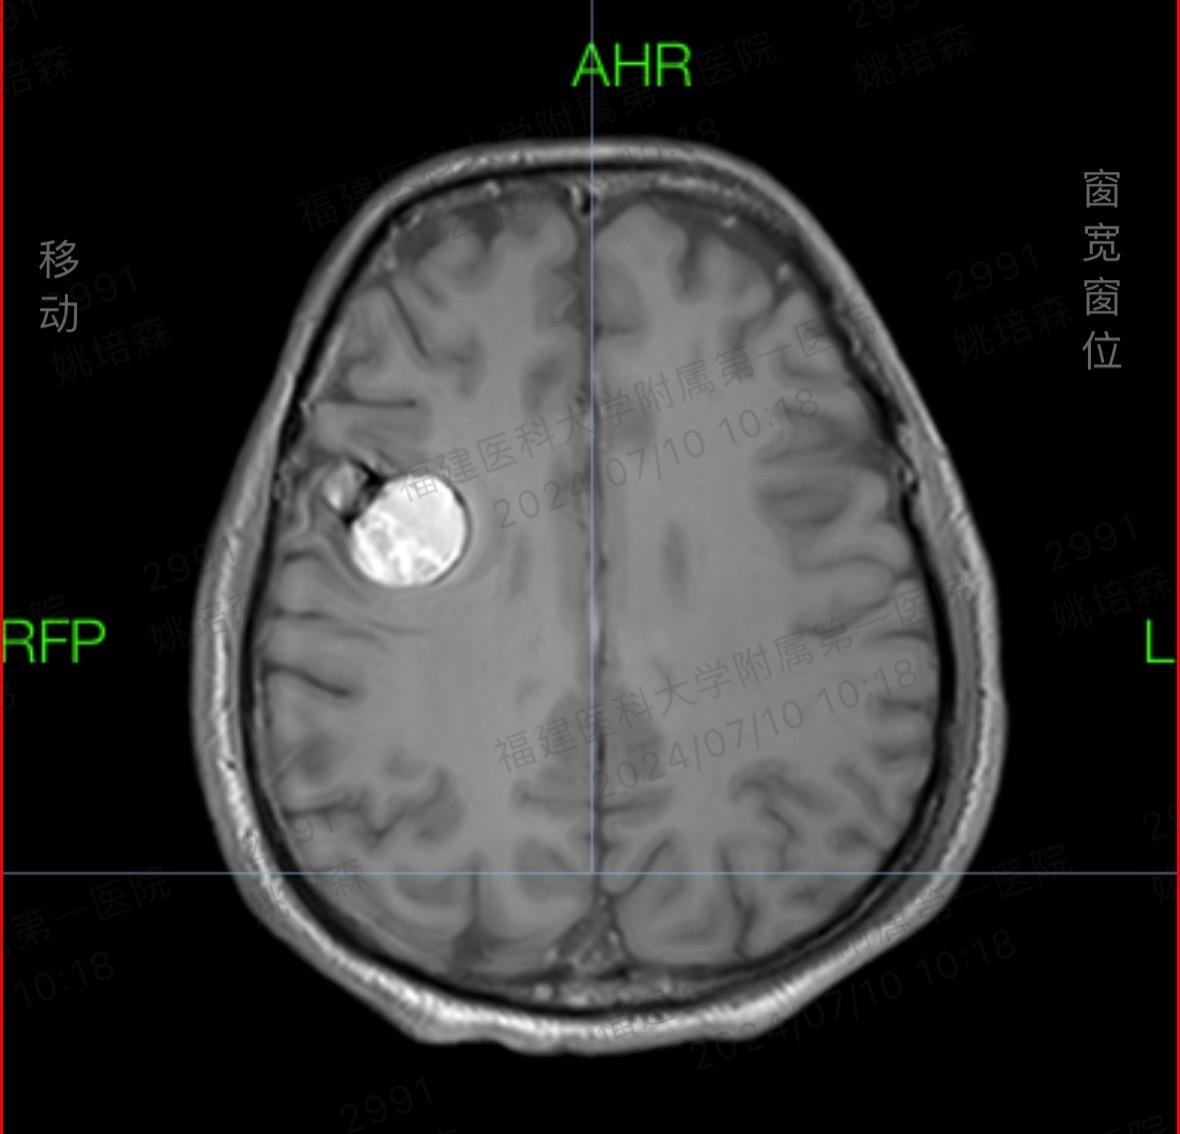

脑内血管瘤合并癫痫。其实海绵状血管瘤如果在非功能区手术难度一般,但是如...